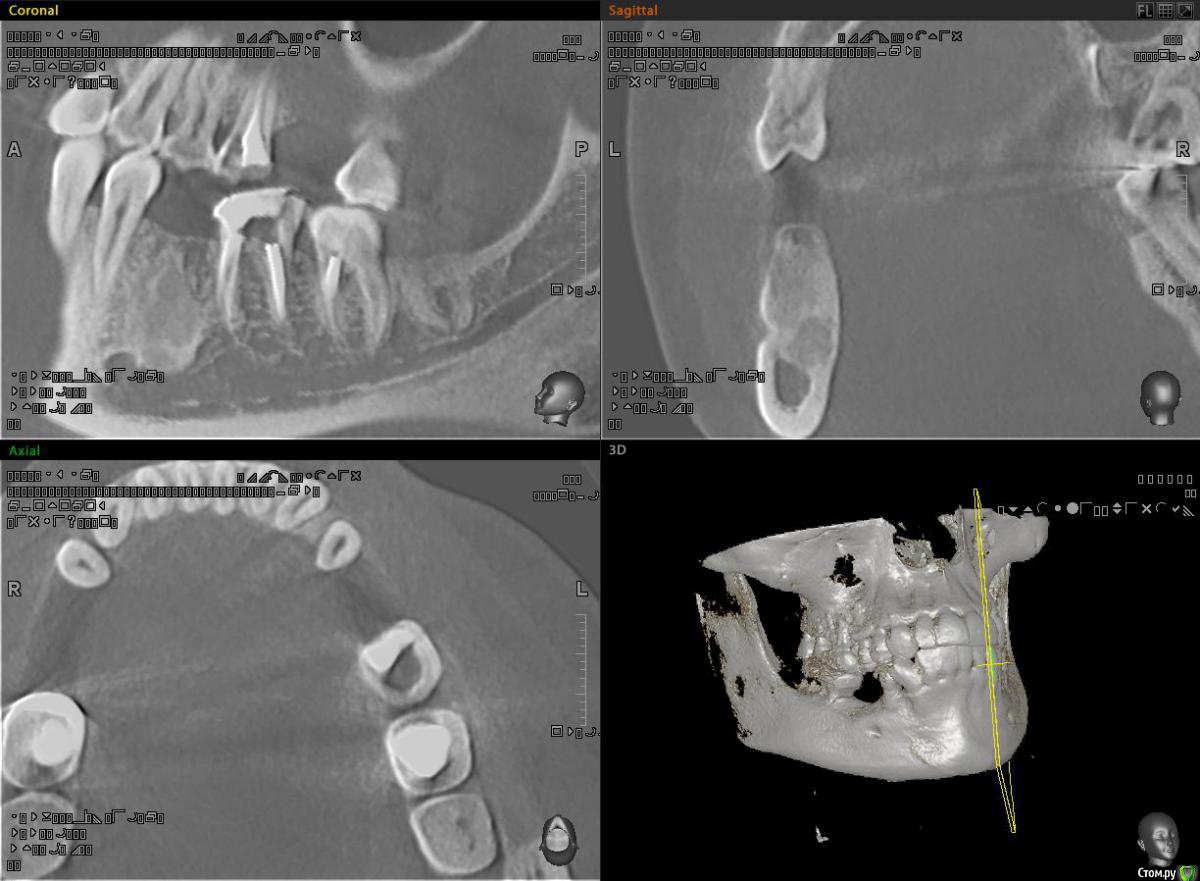

alekszander Опубликовано 16 декабря, 2015 Поделиться Опубликовано 16 декабря, 2015 Почитал тему про цементомы и посмотрел, чтов зависиости от года тактика менялась))Направлен пациент на возможность имплантации в области зуба ... ну назовем его 3.6.На Кт вот такой рисунок кости. Как понимаю, максимум что там было - молочный зуб,т.к. 4.6-4.8 на месте.1. Есть ли смысл туда сверлиться?2. Есть ли смысл отправить на гистологию,если не будем сверлиться и ортопед поставит мост?3. Главный вопрос Что это? Цементома? Ссылка на комментарий

ILGAMSA Опубликовано 16 декабря, 2015 Поделиться Опубликовано 16 декабря, 2015 Это не цементома, это участок остеосклероза. 2 Ссылка на комментарий

faity Опубликовано 16 декабря, 2015 Поделиться Опубликовано 16 декабря, 2015 сомневаетесь- вместо пилота возьмите тонкий трепан и на гисту кость, вращающийся инструмент берите одноразовый, по такой кости любой потом в топку улетитимплантируйте и ничего не бойтесь Ссылка на комментарий

Карен Аванесов Опубликовано 16 декабря, 2015 Поделиться Опубликовано 16 декабря, 2015 Очень плотный, я ставлю в такую кость цилиндрические имплантаты с заглушкой Ссылка на комментарий